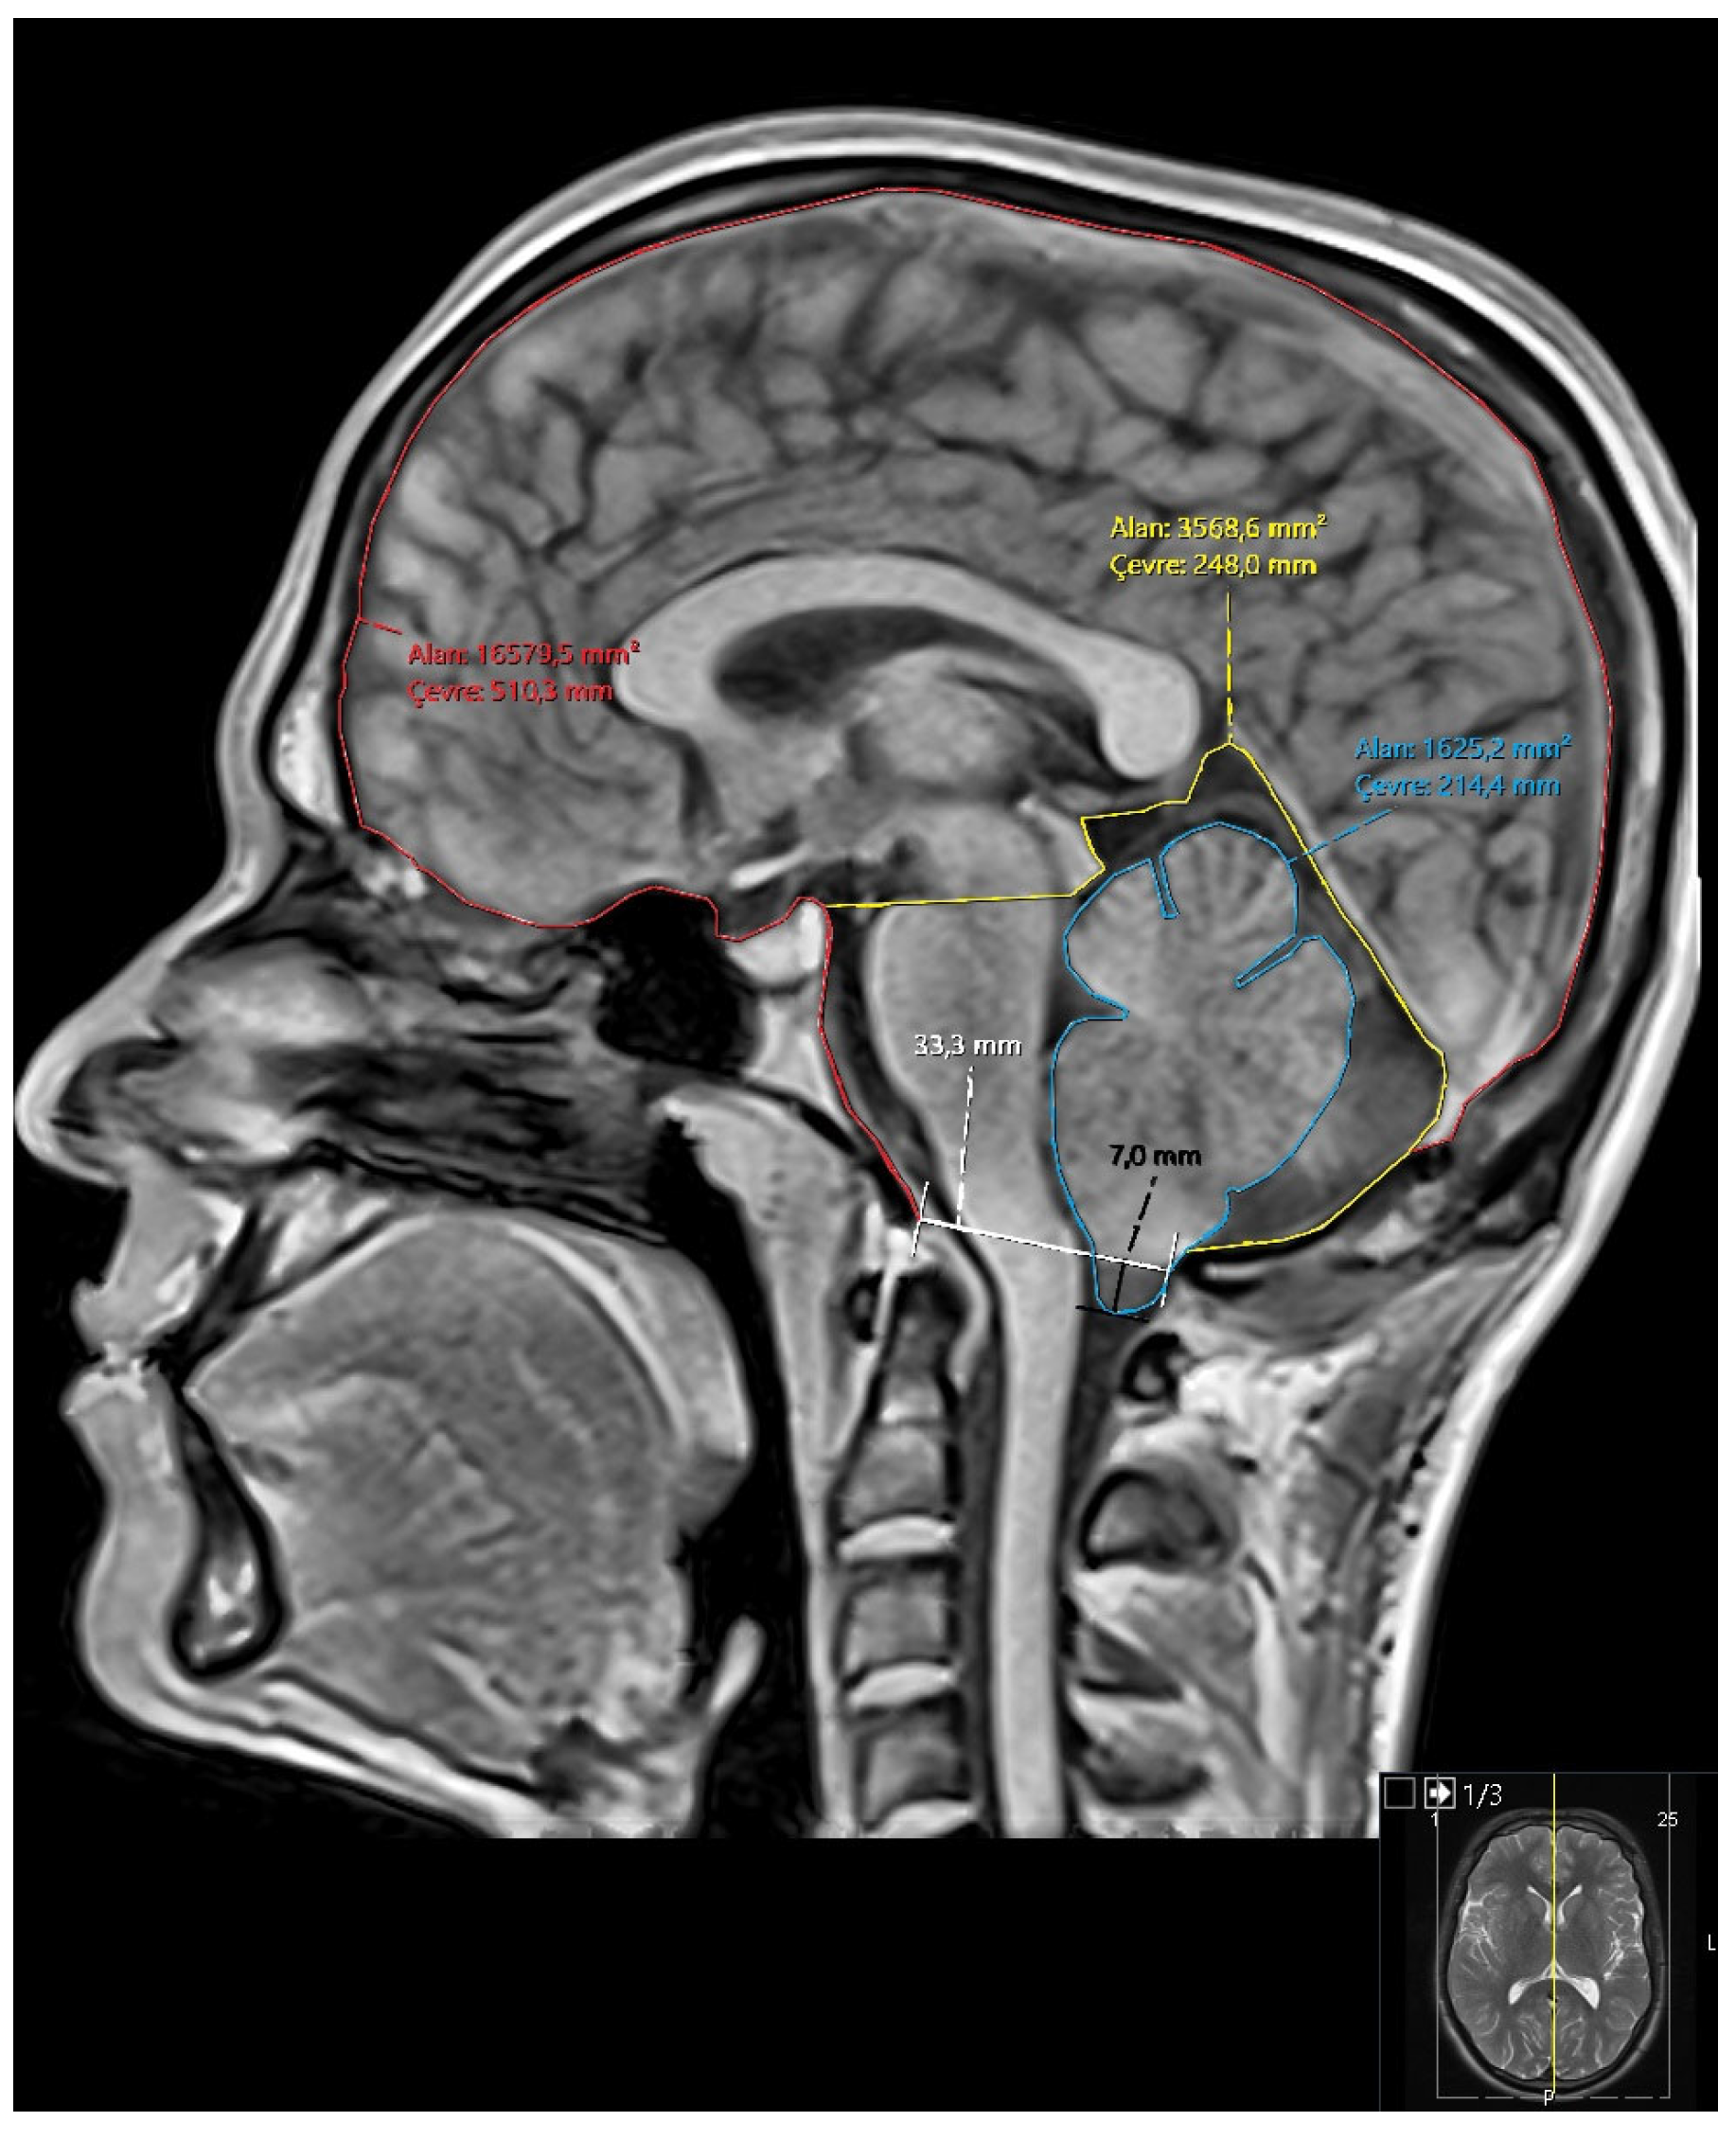

- Diameter of the foramen magnum

- Degree of tonsillar descent (for Groups 2 and 3)

- Area and perimeter of the posterior fossa

- Area and perimeter of the cerebellum

- Area and perimeter of the intracranial cavity

- Ratios: cerebellum/posterior fossa, posterior fossa/intracranial area, cerebellum/intracranial area (Figure 1)